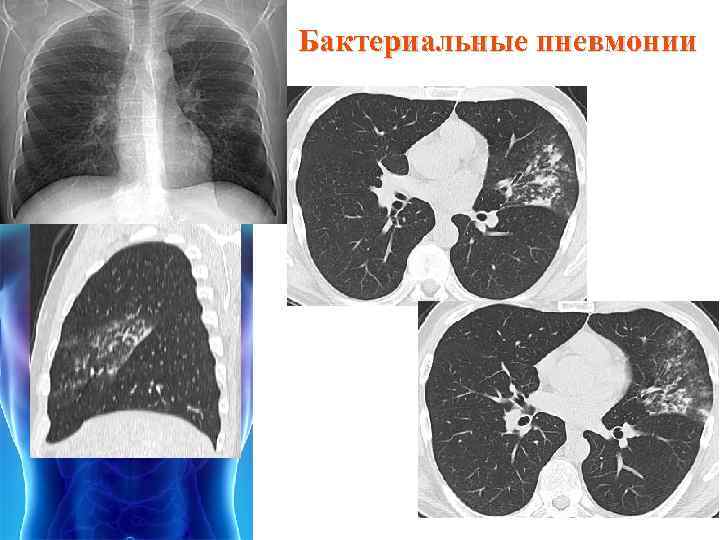

Фотографии бактерий, вызывающих бактериальные пневмонии у животных